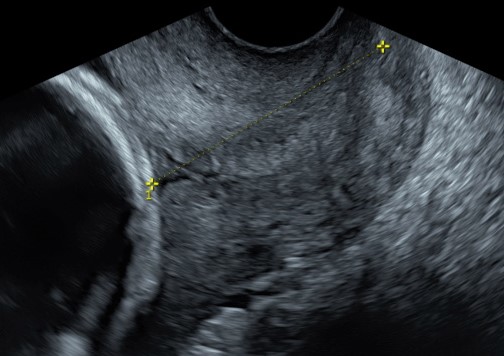

Un passaggio importante è la valutazione del collo dell’utero, che ha la funzione di sorreggere l’utero che cresce con il suo prezioso contenuto. Con l’ecografia transvaginale è infatti possibile ottenere una misurazione della lunghezza della cervice uterine e vedere se sono presenti modificazioni dell’orifizio interno, che sarebbe la porta di ingresso verso l’utero.